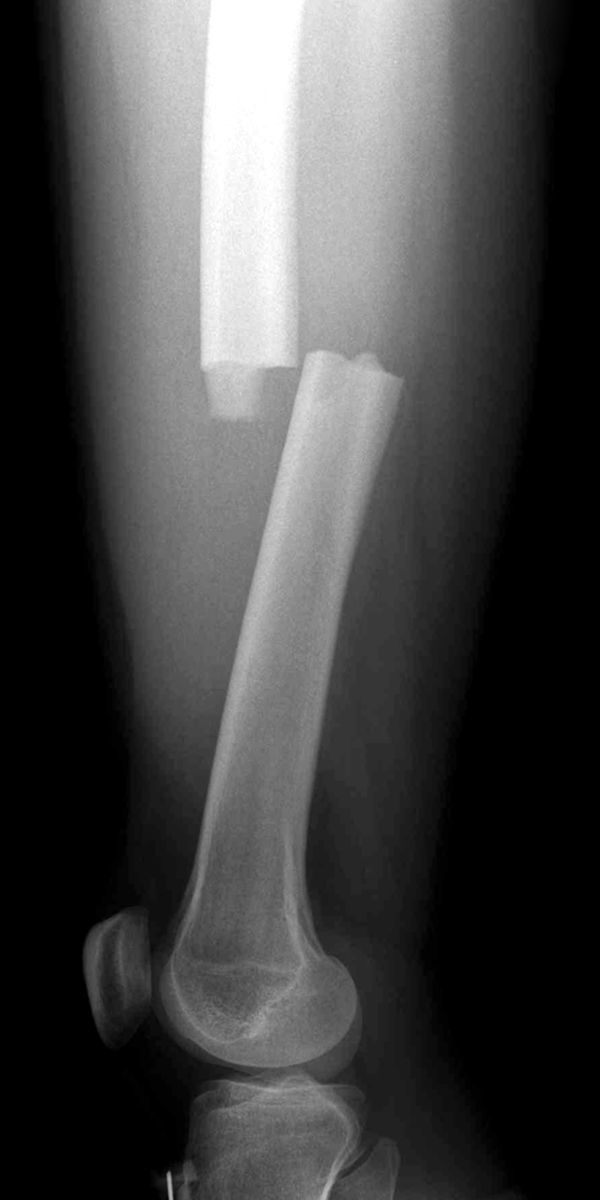

What kind of fracture is this, of what bone, what view is it taken from and describe the displacement?

Transverse Fracture

Femur

Lateral view

Posterior displacement with some shortening